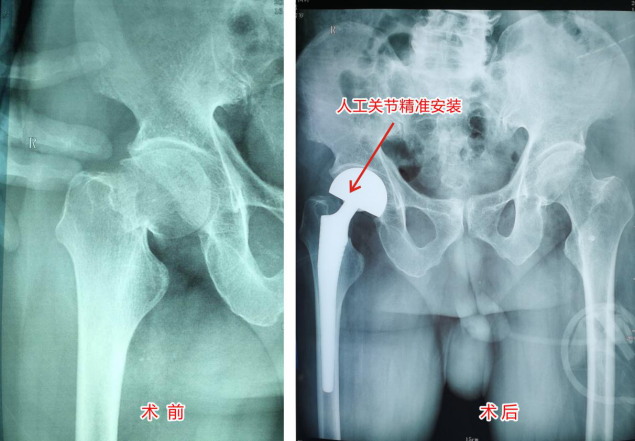

手术非常成功,图为术后检查结果

入院后第四天,在麻醉科和手术室的密切配合下,由外科陈荣生主任医师主刀,两位骨科主治医师助手协力,快捷顺利地实施了人工髋关节置换手术,效果精准。

我院黄汉荣院长、刘建安副院长得知此种情况后,由医务科组织全院讨论,并先后请内科、麻醉科主任会诊,指导围术期治疗。很快患者血压接近正常,一般情况改善,征得患者家人的同意,决定实施生物型进口陶瓷材料人工髋关节置换手术。以期尽早消除老人的痛苦,早日离床活动,避免并发症的发生,可望得到康复。